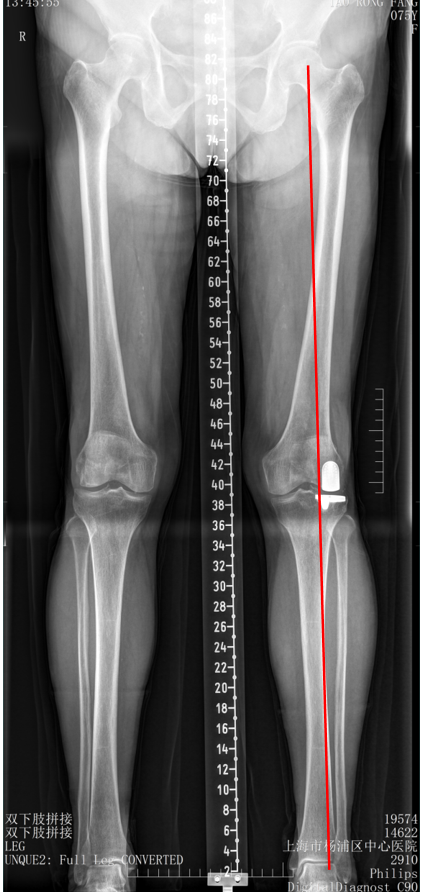

双间室OA行Bi-UKA术后内侧假体周围骨折ORIF

六、二期双单髁置换LINK:registered: SLED假体位置

1、内侧UKA术后外侧间室进展性OA

2、外侧UKA术后内侧间室进展性OA